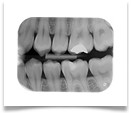

Nel nostro Studio impieghiamo un sistema radiografico computerizzato, il Vista Scan Plus della Dürr che consente di ottenere immagini di alta qualità (vedi confronto analogico/digitale) con dosi radiogene sensibilmente più basse per il paziente.

Con Vistascan Plus siamo in grado di ottenere, nel giro di pochi minuti, tutte le immagini che ci servono per un corretto ausilio diagnostico: bitewing, endorali, ortopantomografie, teleradiografie.